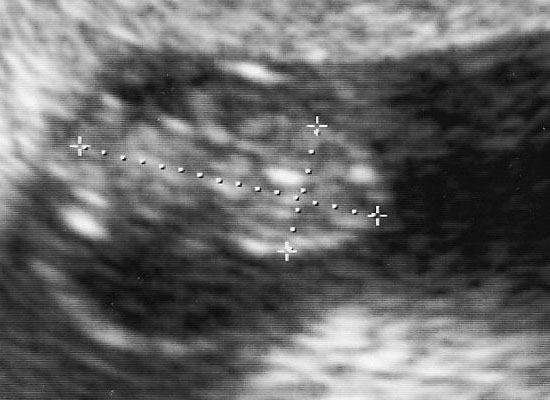

『胎のうがうっすらと確認出来る程度なんで、まだはっきりとわからない』と言われてたんですね。

しかしとりあえず、丸い粒は見えて着床してるって事はわかったんで、旦那には『育つかどうかわからんけどとりあえず出来てるっぽい』と説明しときました。

胎のうやら、心音は結構早めに確認出来てたんですけどね。

内視鏡写真は毎度いただけます。